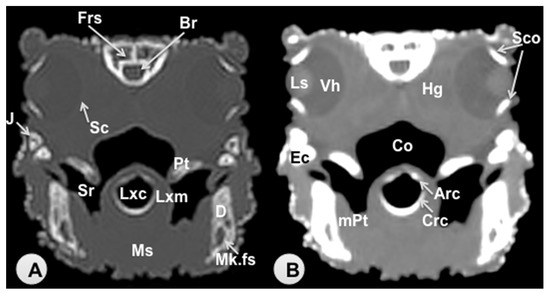

3.1. Transverse Computed Tomography Images